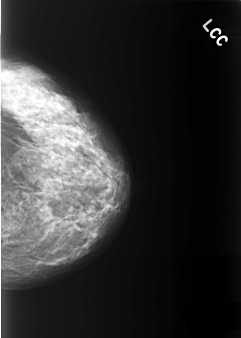

C_0337_1.LEFT_CC

LEFT_CC LINES 5408 PIXELS_PER_LINE 3848 BITS_PER_PIXEL 12 RESOLUTION 50 NON_OVERLAY